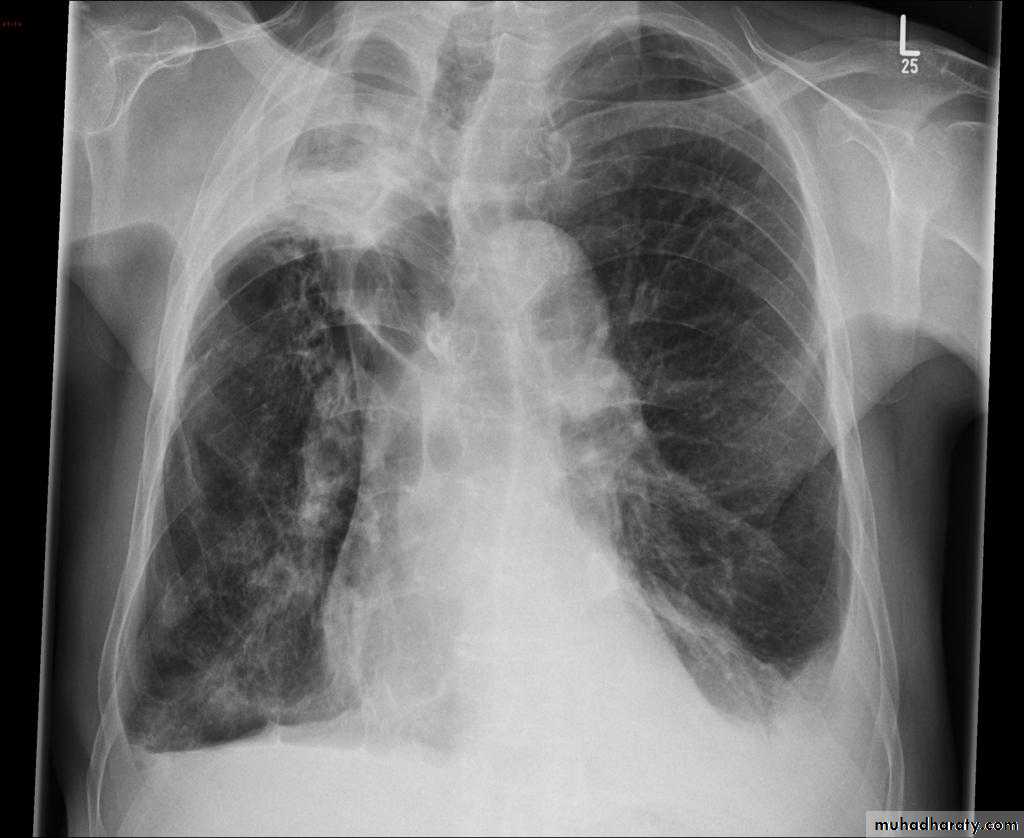

Plain radiograph

Chest x-rays are usually abnormal

1. Tram-track opacities are seen in cylindrical bronchiectasis, and

2. air-fluid levels may be seen in cystic bronchiectasis.

Honey comb shadow

3.Overall there appears to be an increase in bronchovascular markings, and bronchi seen end on may appear as ring shadows .

4.Pulmonary vasculature appears ill-defined, thought to represent peri bronchovascular fibrosis .